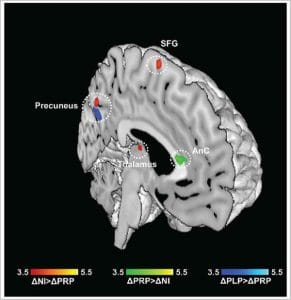

V úlohách rozpoznávania nepríjemných podnetov sa medzi účastníkmi z placebovej alebo kontrolnej skupiny a šťastnejšími účastníkmi zo skupiny s probiotikami prejavil jasný rozdiel – doslova: Funkčná analýza magnetickej rezonancie ukázala, že určité oblasti mozgu boli silnejšie prekrvené, a teda viac aktivované. Konkrétne sa aktivovali oblasti mozgu zodpovedné za výkonnosť pamäte, zlepšenie motorických schopností a vyššiu pozornosť. To sa prejavilo aj v miere rozpoznania: zatiaľ čo kontrolná skupina alebo skupina s placebom rozpoznala menej ako 70 % opätovne zobrazených obrázkov, v skupine s probiotikami bolo rozpoznaných dokonca viac ako 85 % obrázkov.

Okrem toho sa skúmali emocionálne rozhodovacie procesy. Aj v tomto prípade sa prejavil významný pozitívny účinok: účastníci zo skupiny užívajúcej probiotiká boli vysoko koncentrovaní, a preto boli vo svojom rozhodovaní sebavedomejší a jednoznačnejší.

Táto štúdia poskytla jasné dôkazy o tom, že podávanie tohto konkrétneho viacdruhového probiotika viedlo k výraznému zlepšeniu koncentrácie a pamäti, ako aj k pozitívnym emocionálnym dojmom a že užívatelia probiotík boli vo svojich rozhodnutiach výrazne sebaistejší a jasnejší.

© Bagga et al. (2018), DOI 10.1080/19490976.2018.1460015